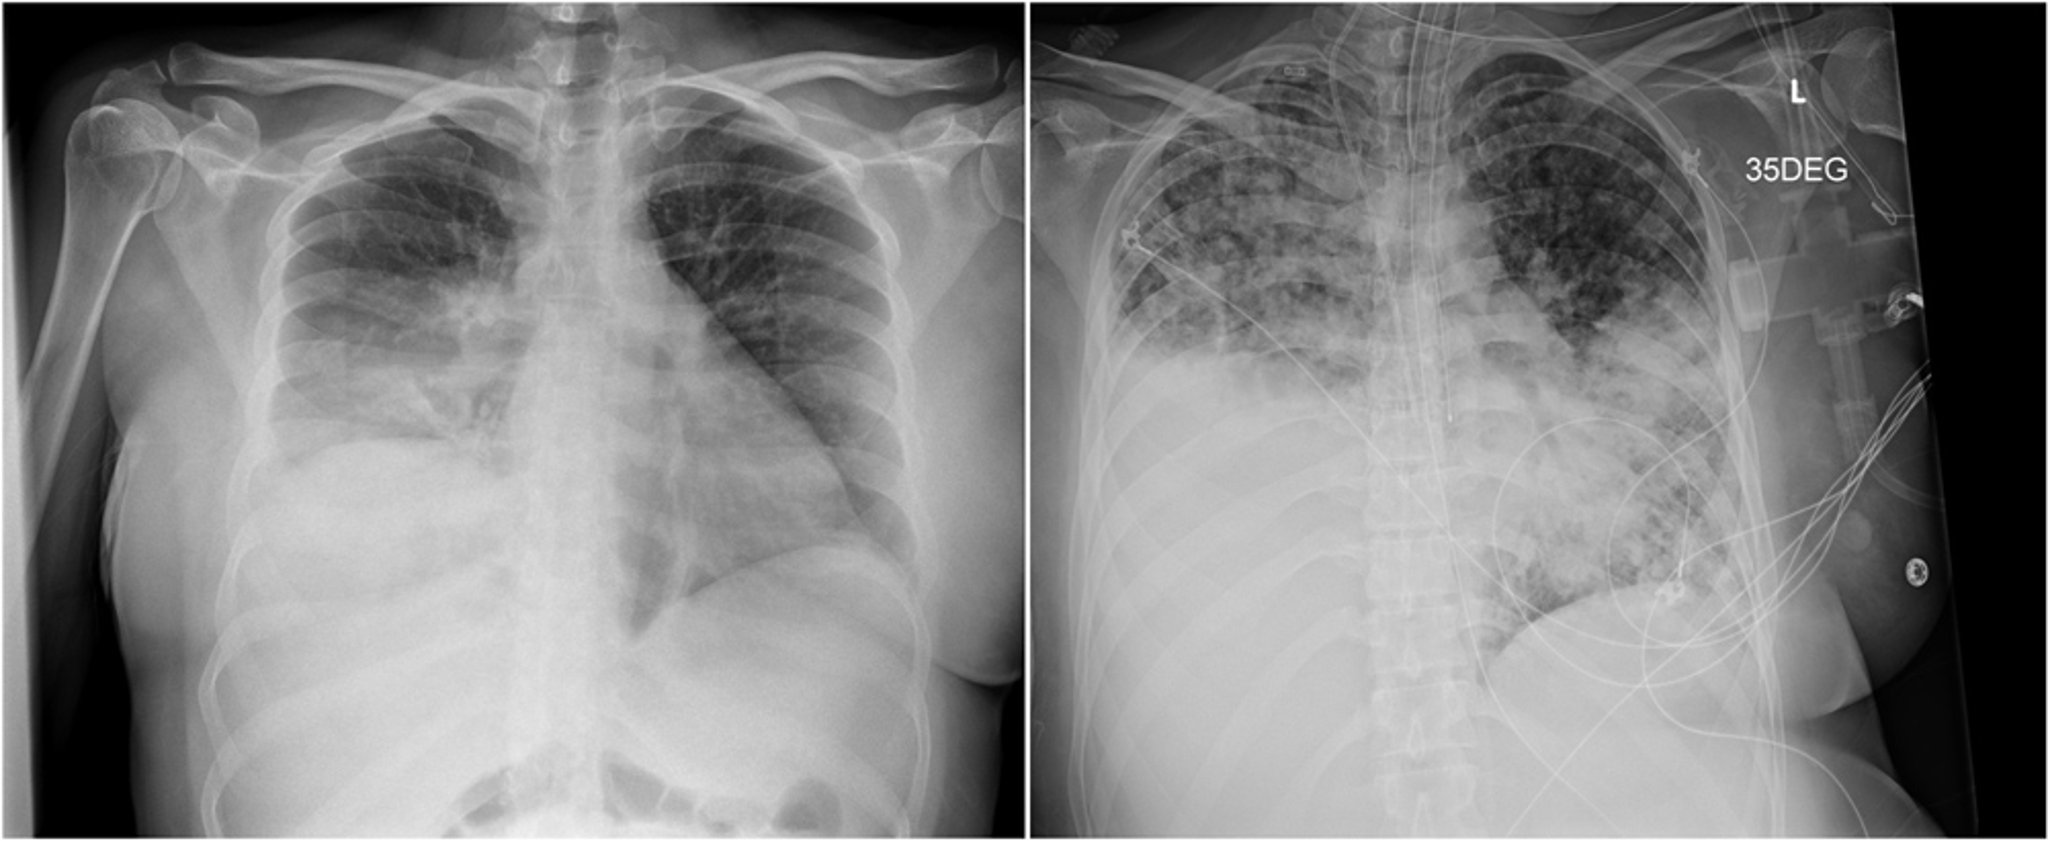

Бластомикоз

Рентгенограмма слева показывает уплотнение в нижней доли правого легкого, которое было ошибочно принято за бактериальную пневмонию. Рентгеновский снимок справа, сделанный спустя три недели, показывает прогрессирование заболевания с неоднородными двусторонними затемнениями в воздушном пространстве и массивным уплотнением в нижней доле правого легкого.

Images courtesy of Paschalis Vergidis, MD, MSc.